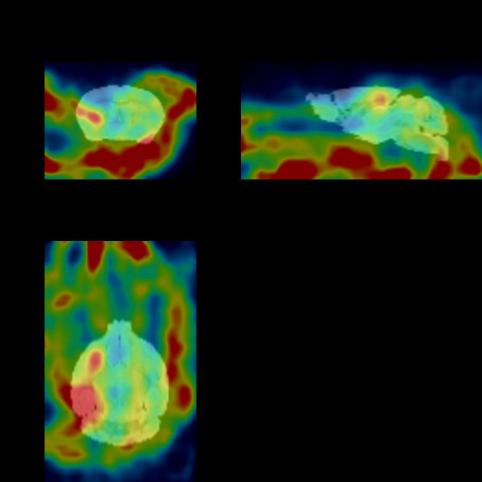

The figure below shows the 30min imaging image